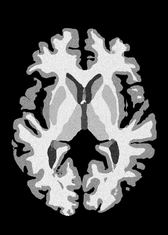

4.2 Registration to a 100 micron ex-vivo brain MRI volume

To showcase the efficacy of our method on real large scale images, we register a 250 in-vivo MRI image (Lüsebrink et al., 2017) to a 100 ex-vivo FLASH human brain volume (Edlow et al., 2019). This represents an inverse problem with more than 11.2B optimizable parameters (compared to 20M for clinical datasets), or 44.8GB of GPU memory. The entire problem does not fit on most GPUs, necessitating distributed multimodal registration. We optimize a composite transform - affine followed by a diffeomorphic mapping; details can be found in Section E.1. Multimodal deformable registration took 58 seconds on 8 NVIDIA A6000 GPUs, which is unprecedented at this resolution. Fig. 6 shows qualitative results, highlighting the ability to register highly detailed structures such as cerebellar white matter; these structures are not visible at macroscopic scales. The resultant advantages of performing registration at this scale can allow researchers to characterize the neuroanatomy at microscopic resolutions and allow morphometric analysis of cortical layers and subcortical nuclei among other structures.